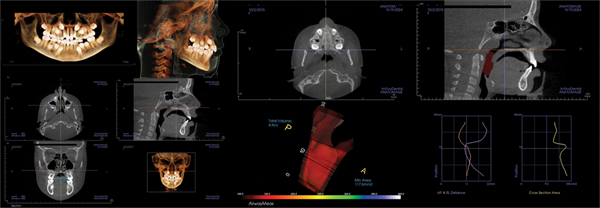

Patient four: Surgical intervention in an adult (Figs. 12–15)

The fourth patient, a 32-year-old woman, presented for an orthodontic examination with a desire to align her teeth. During the examination and discussion, she reported poor sleep and a prior diagnosis of OSA. Her AHI was 77.

CBCT evaluation confirmed these findings. The skeletal examination revealed a slight Class III tendency with a balanced smile.

The panoramic X-ray showed a full complement of teeth with no third molars. The lateral X-ray confirmed the Class III tendency. Her airway MCA measured 74 mm, and her palatal width was 33 mm.

The patient was referred for maxillomandibular advancement (MMA) surgery, with orthodontic preparation. Following surgery, her sleep normalized, with a post-treatment AHI of 1.5 and an MCA of 289 mm. Her facial appearance was relaxed and well-balanced. The patient indicated she would make the same decision again.